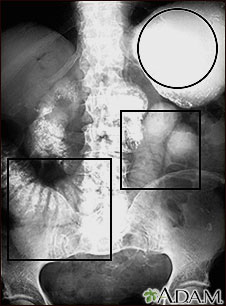

Ileo: Radiografía del estómago e intestino distendido

Esta radiografía abdominal muestra un estómago lleno de líquidos y una dilatación (distensión) del intestino delgado, ocasionados por una obstrucción en los intestinos. El paciente ingirió (series del tracto GI superior) un medio de contraste (bario) que es visible en las radiografías.